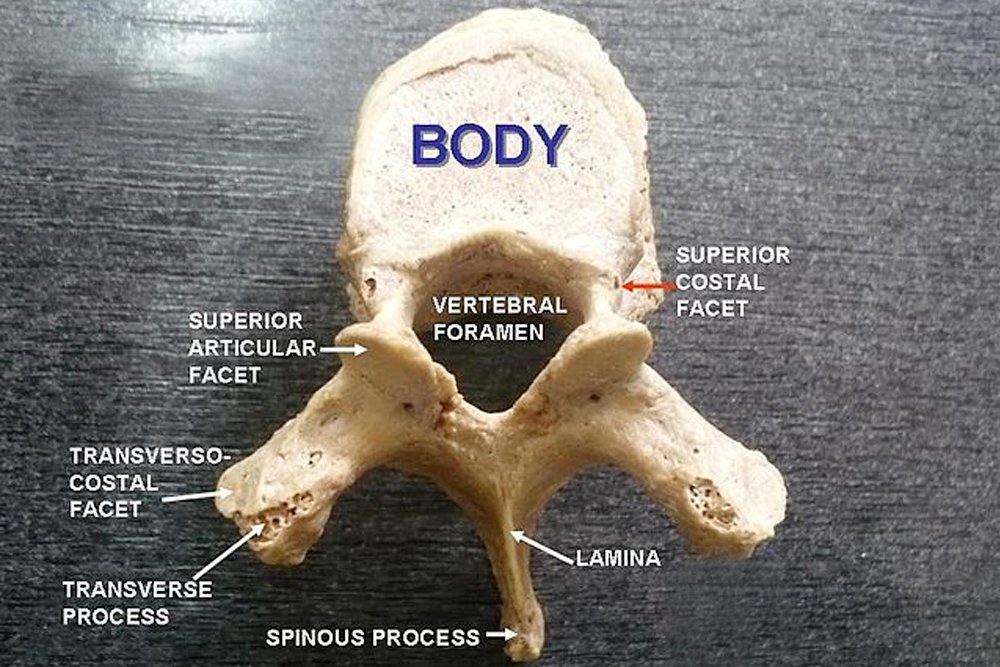

The typical structure of a vertebra is illustrated below:

There is a part of the body, the vertebral foramen, where the spinal cord, the process that handles nerves from the brain, passes through. Several other processes exist in the vertebral bone, such as the spinous process, seen in the picture above. These processes are elongated, bony protrusions that help in association and articulation with muscles and other bones.

When you think of the thoracic region, the first thing that comes to mind is the rib cage. The rib cage lies in the thoracic region of the body, and the thoracic vertebrae have a slight modification in order to articulate with the ribs. This modification comes in the forms of demifacets. Facets are basically flattened surfaces of a bone. A demifacet is half of a facet, and is meant for articulation with the ribs and coastal cartilage. The vertebrae have both superior and inferior demifacets. Each rib articulates with the corresponding vertebra and the vertebra above it.